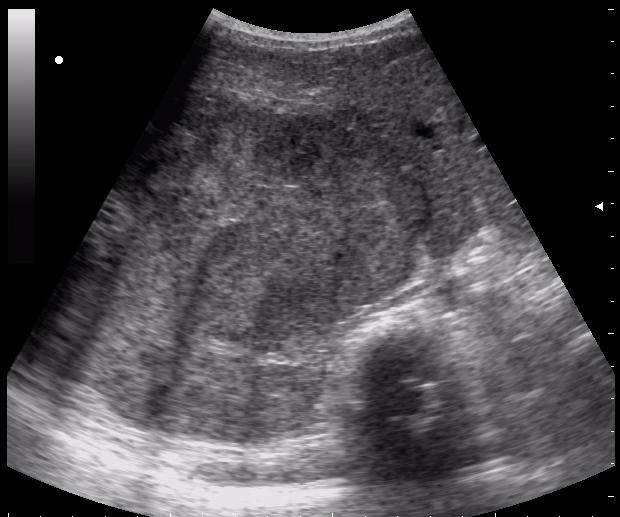

(девушке 23 года. фиброматоз матки)

ещё раз - это матка 23-летней девушки. то есть, ВСЁ это, то что Вы видите, да-да, на весь экран - это матка.

Диагноз - фиброматоз. направлена строго на север и налево. к соседям. (онкодиспансер)